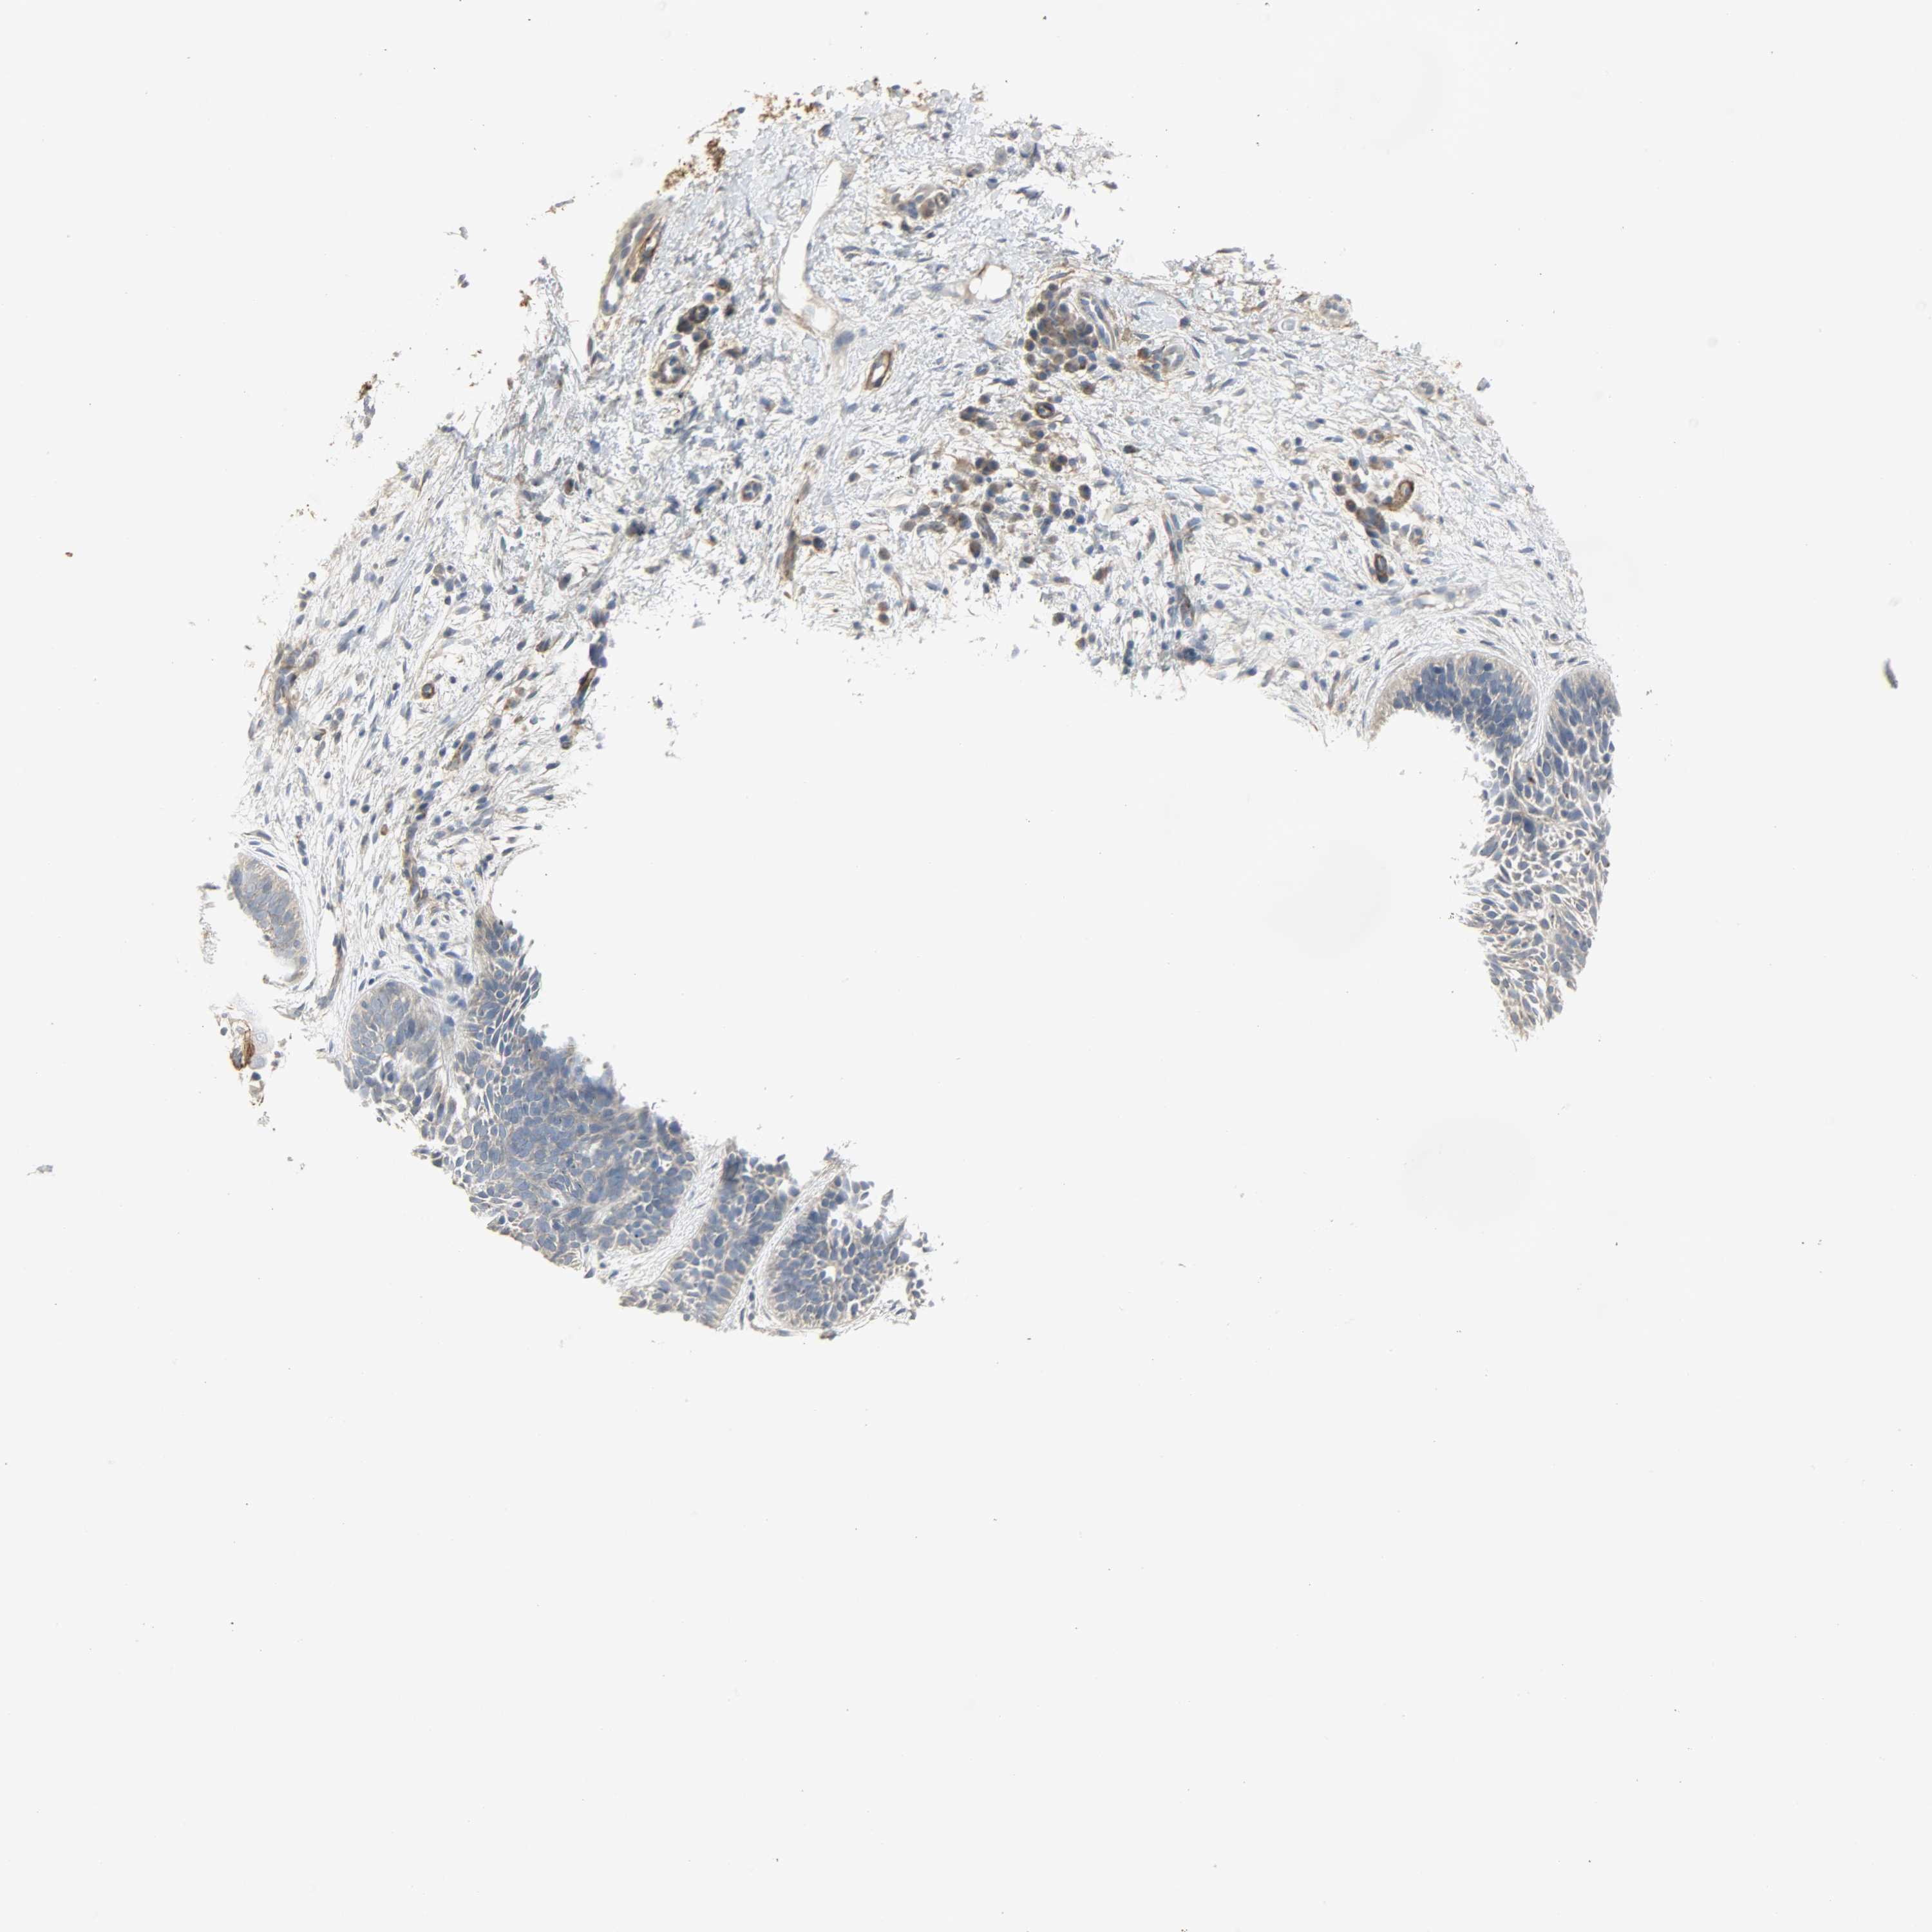

SKIN CANCER - Protein expressioni

A mouse-over function shows sample information and annotation data. Click on an image to view it in a full screen mode. Samples can be filtered based on level of antibody staining by selecting one or several of the following categories: high, medium, low and not detected. The assay and annotation is described here.

Each image is clickable and will lead to virtual microscopy that enables deeper exploration of all samples and also displays staining intensity scores, fraction scores and subcellular localization as well as patient and tissue information for each sample.

Antibody HPA005128

Squamous cell carcinoma, NOS

Basal cell carcinoma